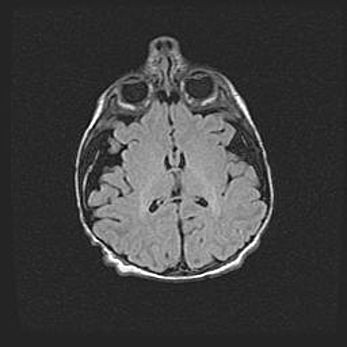

Церебральная ишемия II.

Возраст: 5 дней

Вес: 3400 г

Пол: женский

Окружность головы: 35 см

Срок гестации: 39 недель

Церебральная ишемия – это заболевание, характеризующееся недостаточностью (гипоксией) либо полным прекращением (аноксией) снабжения мозга кислородом по причине закупорки одного или нескольких сосудов. Это приводит к  что метаболическим расстройствам различной степени тяжести в тканях головного мозга, развитию коагуляционных некрозов и гибели нейронов.